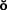

The laterally positioned pedicle graft40,41 (Fig. 6-14) is used for an area of recession or lack of attached gingiva on a single tooth when there are adequate amounts of keratinized gingiva in adjacent teeth or edentulous spaces. Although several studies have proposed techniques in which free (detached) autogenous gingival grafts are used for root coverage,42-44 the pedicle graft can be a more predictable treatment because of maintenance of the blood supply to the pedicle.

Fig. 6-14 Laterally positioned pedicle graft. A and B show localized recession around the left mandibular central incisor. The lateral incisor has an adequate band (width) of keratinized tissue, so it is suitable as a donor site. C, Bed preparation of the recipient site. An incision is made obliquely toward the site. D, Releasing incision at the distal of the donor site. The graft is rotated into position over the recipient site. E, Flap sutured in position. A free autogenous gingival graft may be used to cover the donor site. F, The healed graft. There is almost always some loss of attachment at the donor site (average, 1 mm).

The recipient site is prepared by excising 1 to 3 mm of split-thickness marginal gingiva bordering the recession area. At the donor site, oblique vertical incisions are placed in the mucosa as far apically as possible to ensure adequate blood supply for the graft. The apical area of the donor tissue is made wider than the coronal area. The flap is mobilized and placed on the recipient site and sutured into place. A free gingival graft may be needed to cover the donor site. A surgical dressing is placed over the site.